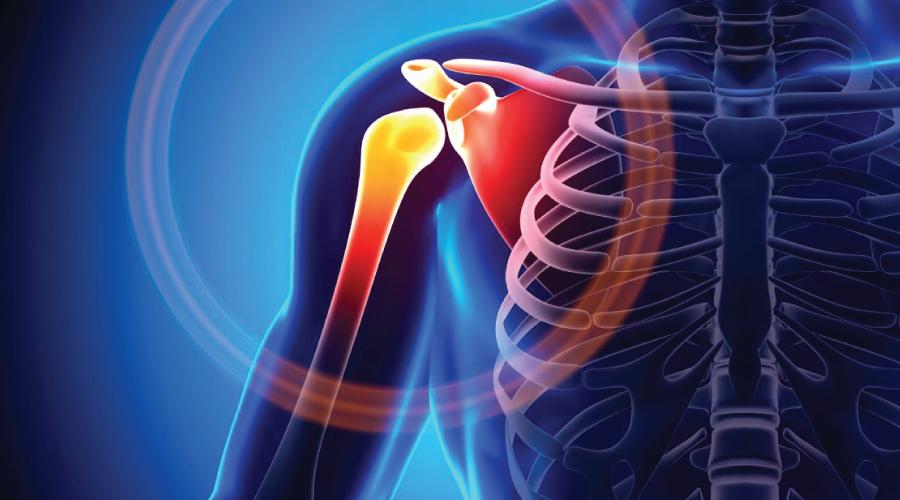

Травми та захворювання плечового суглоба: причини, симптоми та лікування

Плечовий суглоб — один із найбільш рухливих в організмі людини, але саме ця рухливість робить його вразливим до різних травм та захворювань.